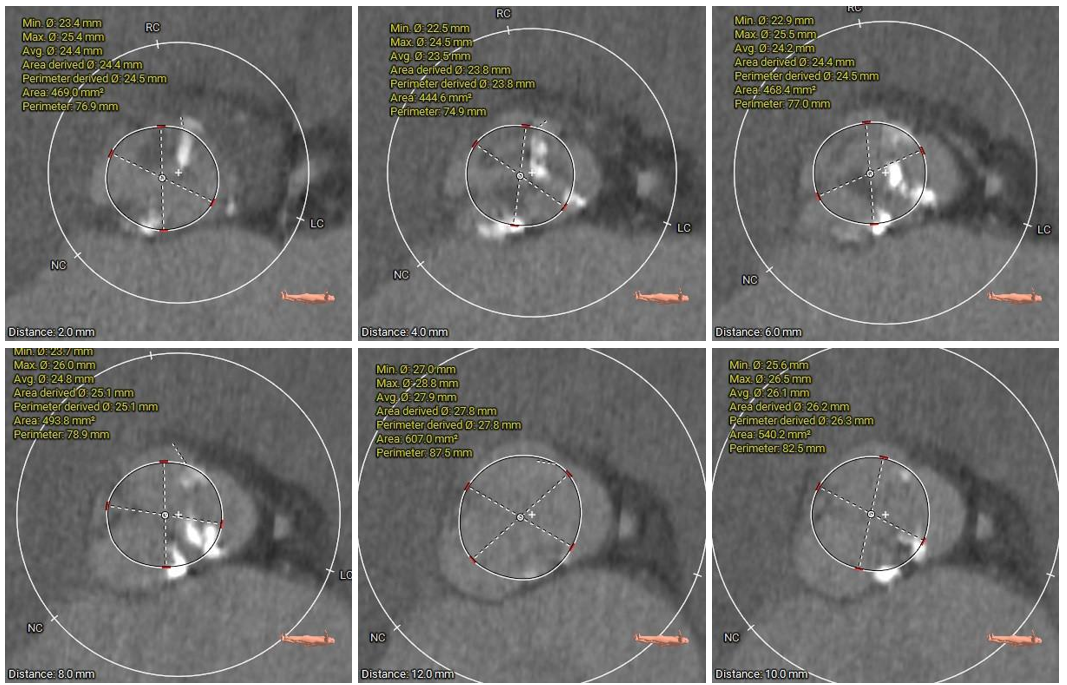

主动脉根部测量

本例患者为主动脉瓣中重度狭窄伴重度反流,患者病程约十余年,曾反复出现严重心衰多次住院治疗,保守治疗效果欠佳;期间两次到上级医院住院,因惧怕外科开胸手术风险都未行瓣膜置换手术。此次患者再次出现严重心衰,内科保守治疗效果不佳,王才安主任团队在经过充分细致的术前评估,结合多学科团队讨论意见后考虑为患者实施经导管主动脉瓣置换(TAVR)术。术前CT分析提示患者为Type1型二叶式主动脉瓣,L-R间可见钙化融合脊,瓣环径较大,达到28.3mm,对于瓣膜锚定及封堵效果都提出了较高要求;另外,患者为横位心、主动脉弓部锐利,弓距较短,需要输送系统具有良好的过弓、跨瓣性能,也对术者快速、精准的操作能力及手术团队的密切配合提出了更高的要求。